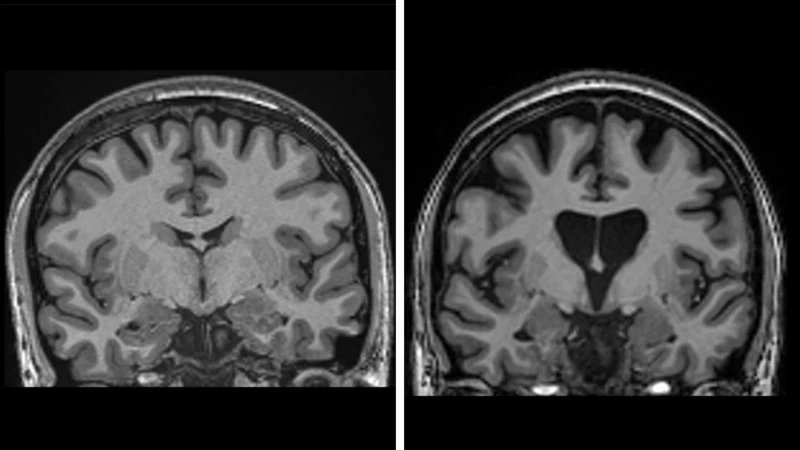

Жаңа әдістің сынақтарын ұйымдастырған uniQure компаниясы АҚШ пен Еуропада 2022 жылы ота жасалып, кейін үш жыл бойы бақылауда болған ерікті пациенттерде Хантингтон сырқатының даму қарқыны 75%-ке баяулағанын мәлімдеді.

Хантингтон ауруының алғашқы белгілері әдетте 30 жастан кейін пайда болады. Науқас бұл сырқатпен 20 жылдан артық өмір сүрмейді.